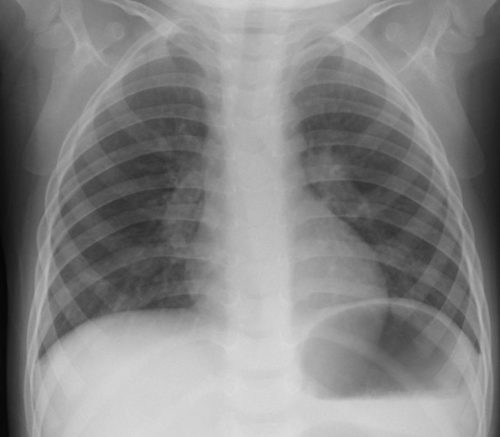

[区域性分布と非区域性分布の理解] ***下図を参考に大葉性・小葉性と区域性・非区域性を混同しないこと。 [マイコプラズマ肺炎陰影の成り立ち] [参考1]マイコプラズマ肺炎の2型 [参考2]マイコプラズマ肺炎の2型 [参考3]マイコプラズマ肺炎(肺胞性間質性)

右肺下肺野では肺胞性陰影(浸潤影・airbronchogram)と間質性陰影(水平裂外側の下方への偏移・tram line・線状影等)が混在している。 [参考]右肺は均等影様にみえるが左肺と同じ透過性不良のすりガラス様陰影で間質性の陰影。 [びまん性肺病変の基本型] びまん性肺疾患 間質性陰影と肺胞性陰影